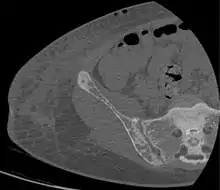

Renal osteodystrophy is usually diagnosed after treatment for end-stage kidney disease begins; however the CKD-MBD starts early in the course of CKD.[1][6] In advanced stages, blood tests will indicate decreased calcium and calcitriol (vitamin D) and increased phosphate, and parathyroid hormone levels. In earlier stages, serum calcium, phosphate levels are normal at the expense of high parathyroid hormone and fibroblast growth factor-23 levels. X-rays will also show bone features of renal osteodystrophy (subperiostic bone resorption, chondrocalcinosis at the knees and pubic symphysis, osteopenia and bone fractures) but may be difficult to differentiate from other conditions. Since the diagnosis of these bone abnormalities cannot be obtained correctly by current clinical, biochemical, and imaging methods (including measurement of bone-mineral density), bone biopsy has been, and still remains, the gold standard analysis for assessing the exact type of renal osteodystrophy.[6][16]

18. 1 2 3 4 5 6 7 Patel, Anish A.; Ramanathan, Rohit; Kuban, Joshua; Willis, Marc H. (2015). "Imaging Findings and Evaluation of Metabolic Bone Disease". Advances in Radiology. 2015: 1–21. doi:10.1155/2015/812794. ISSN 2356-6876.